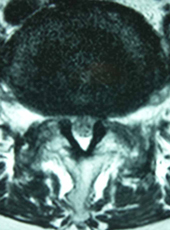

内視鏡手術(MEL法)で術後脊柱管を拡大したところ